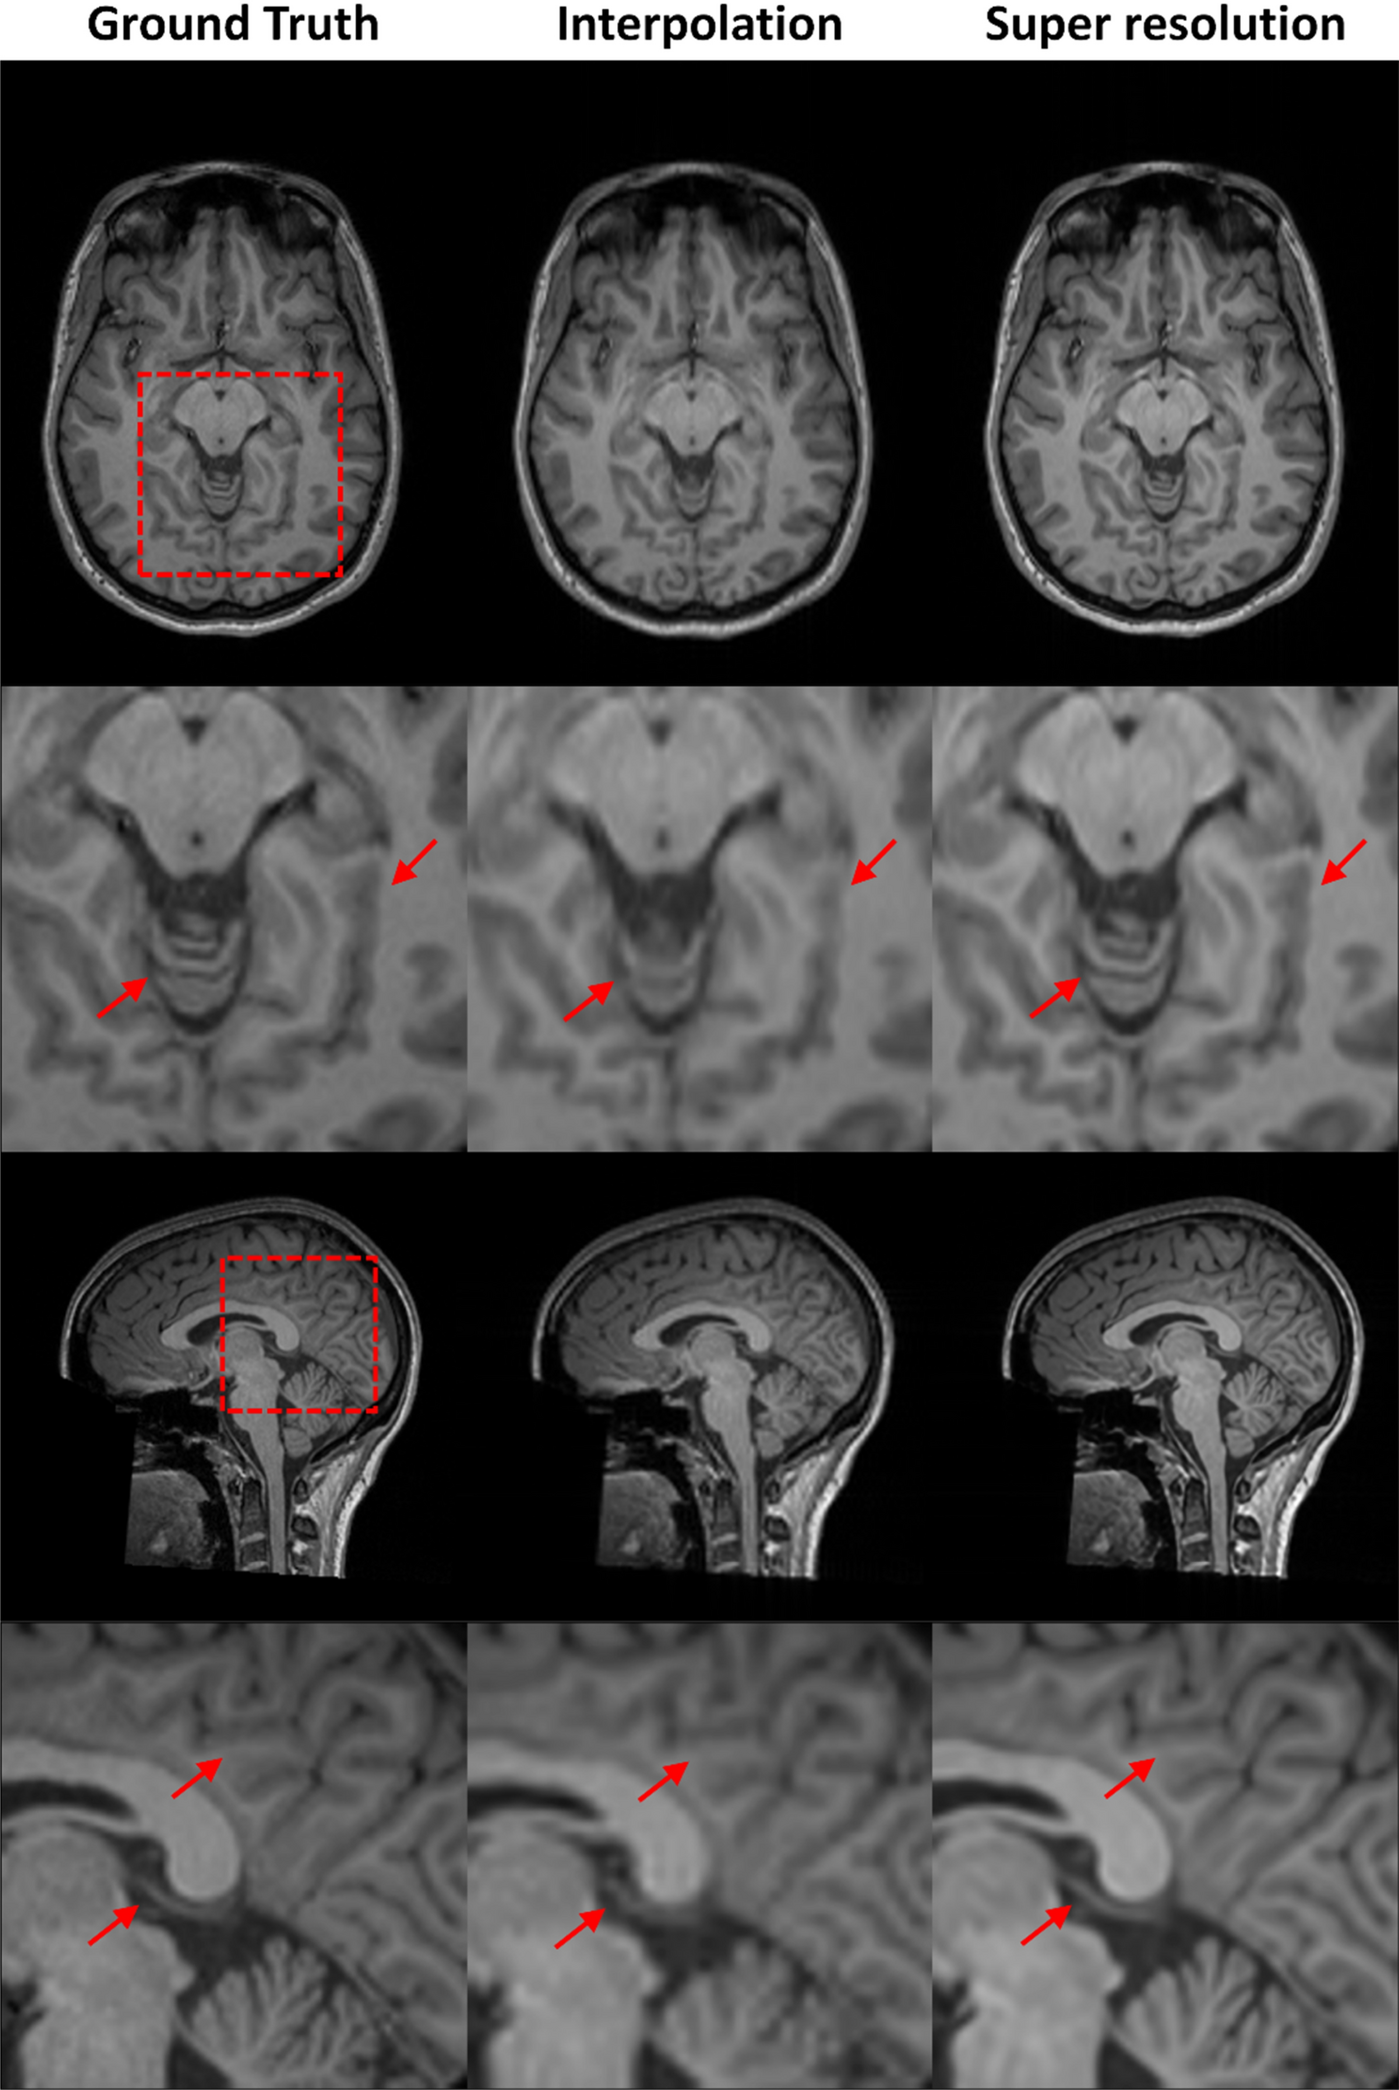

Fig. 9

Super resolution reconstruction on MR-ART dataset with qualitative comparison to tricubic interpolation. Tricubic interpolation results exhibit pronounced blurring and loss of fine anatomical details, with white–gray matter boundaries appearing poorly defined. In contrast, the SRR images produced by the proposed method show a substantial improvement in image sharpness, recovering fine structural details and yielding markedly sharper and more distinct tissue boundaries. These results highlight the advantage of learning-based super-resolution over conventional interpolation, even under out-of-distribution conditions.